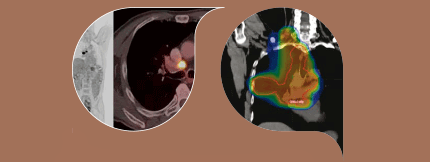

第六章线性肿瘤理疗原理

Tfinazzi辐射肿瘤系VU大学医疗中心,荷兰阿姆斯特丹

塞南市辐射肿瘤系VU大学医疗中心,荷兰阿姆斯特丹